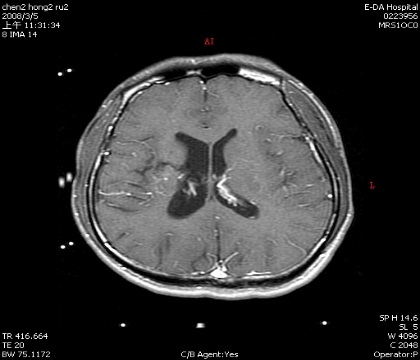

動靜脈畸形

手術前

手術後